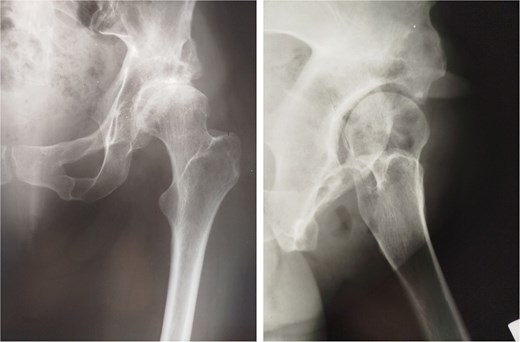

Thirteen years after THA, the 76-year-old patient continued to have a stable asymptomatic hip. Hip radiographs showed unchanged and stable positioning of the acetabular cup and femoral stem, with no measurable subsidence or radiolucent lines around the components (Fig. 4).

Postoperative anteroposterior radiographs of the pelvis 13 years after the THA, showing mechanical stability of the prosthesis with no evidence of loosening. No signs of osteoarthritis are present in the right hip (Tönnis Grade 0).